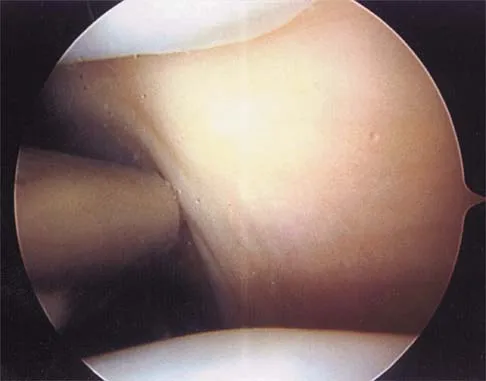

A 21-year-old collegiate pitcher has had pain in his dominant shoulder for the past 3 months despite management consisting of rest, rehabilitation, and an analysis of throwing mechanics. An arthroscopic photograph from the posterior portal is shown in Figure 10. The biceps anchor to the bone was not detached to probing. Treatment of the lesion to the left of the cannula should consist of arthroscopic

Explanation